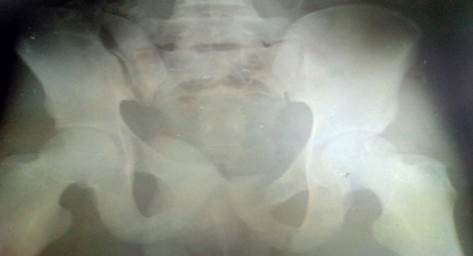

En la radiografía simple en proyección anteroposterior de la pelvis se confirmó la fractura del ilion derecho cerca de la región sacroilíaca y de las ramas púbicas del otro lado o sea Tipo C1 de la clasificación de Marvin Tile (Figura 1).